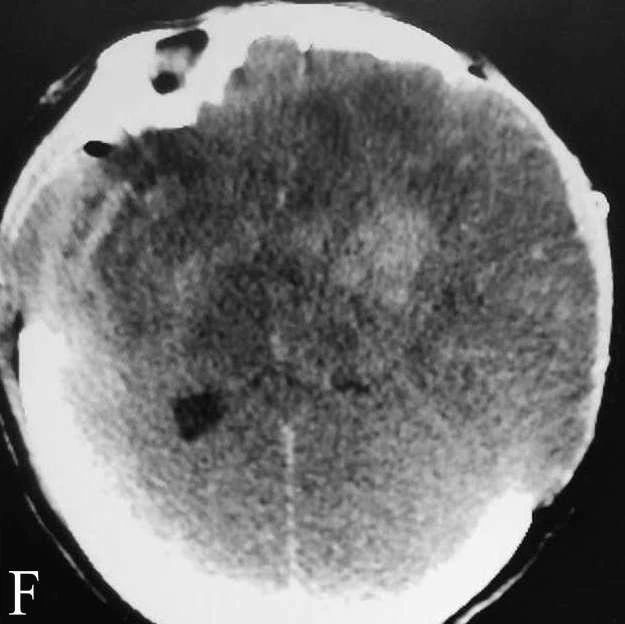

女性,45岁,房颤史,因风湿性心脏病、心功能不全在本院心内科住院期间突发昏迷、抽搐、呕吐0.5h进入卒中绿色通道。查体:中度昏迷,刺痛四肢无活动,NIHSS28分。多模CT提示双侧颈内动脉闭塞, RAPID显示双侧大脑半球低灌注。急诊行球囊导引导管辅助支架取栓,成功开通双侧颈内动脉,ORT时间4h,术后出现严重脑梗塞、脑水肿,双侧大骨瓣减压后仍死亡。

F:去骨瓣减压术后,广泛脑肿胀伴出血